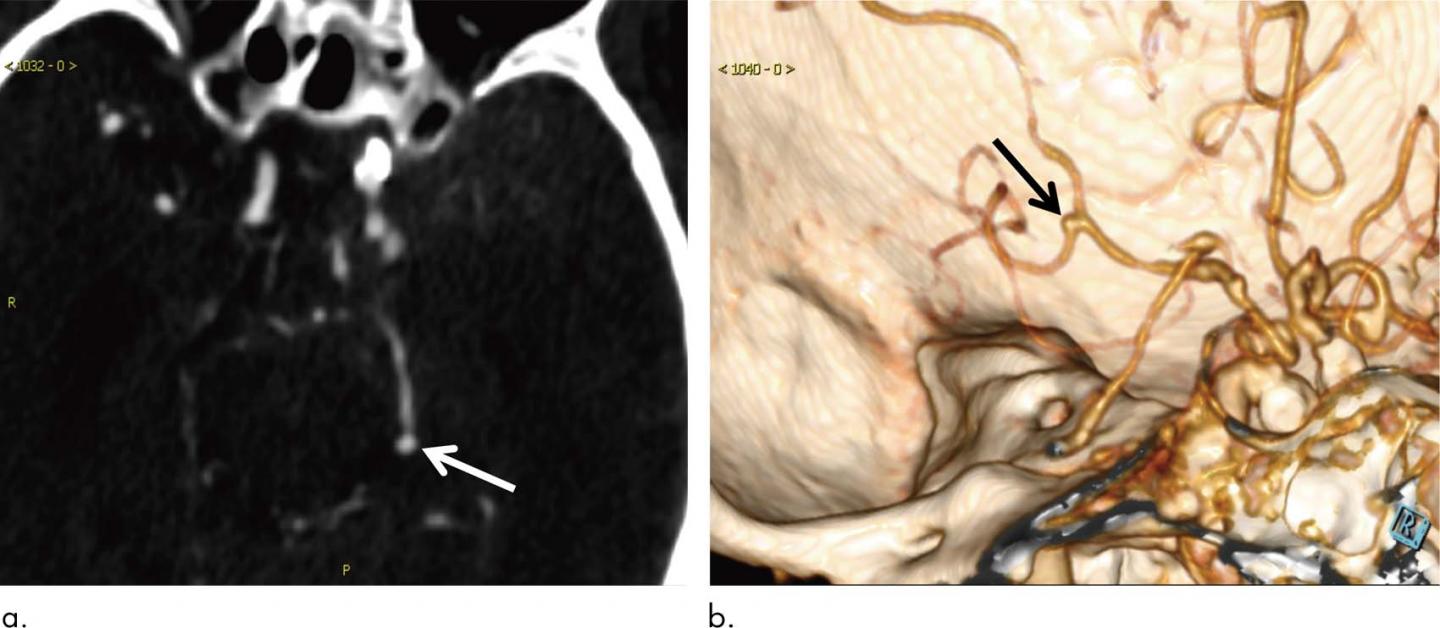

CT angiography is usually the first choice for evaluating cerebral aneurysms. The exam is highly accurate, but cerebral aneurysms can be overlooked on the initial assessment due to their small size and the complexity of the blood vessels in the brain.

In the new study, Dr. Long and colleagues developed a fully automated, highly sensitive algorithm for the detection of cerebral aneurysms on CT angiography images. They used CT angiograms from more than 500 patients to train the deep learning system, and then they tested it on another 534 CT angiograms that included 649 aneurysms.

The algorithm detected 633 of the 649 cerebral aneurysms for a sensitivity of 97.5%. It also found eight new aneurysms that were overlooked on the initial assessment.